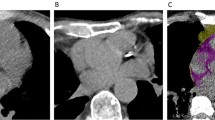

Two readers blinded from clinical data calculated ordinal scores from standard non-gated chest CT studies using the methods described by Shemesh et al. for patients without history of myocardial revascularization [12]. Briefly, the right coronary artery, left main, left anterior descending, and left circumflex arteries were each given a score of 0–3 for presence and extent of calcium with 0 (none), 1 (< 1/3 of the artery length calcified), 2 (≥ 1/3 to < 2/3 calcified), and 3 (≥ 2/3 calcified). These scores were summed across the 4 arteries, providing a range of possible scores from 0 to 12 (see Fig. 1A and B). We calculated the inter-observer variability based on a random sample. Agreement for severity class was high (interclass correlation coefficient = 0.980, p < 0.001).

For the measurement of EAT, we used QFAT software. As previously described [13], QFAT uses convolutional deep learning for fully automated quantification of epicardial and thoracic volumes. Accuracy and reproducibility of QFAT have been previously validated [14, 15]. Contours were reviewed by an expert user and manually modified when needed. Superior and inferior limits of the pericardium were identified as the bifurcation of the pulmonary trunk and the posterior descending artery, respectively. EAT was defined as adipose tissue within the pericardium (see Fig. 1C). Patients with significant artifacts from ICDs or poor acquisition were excluded.